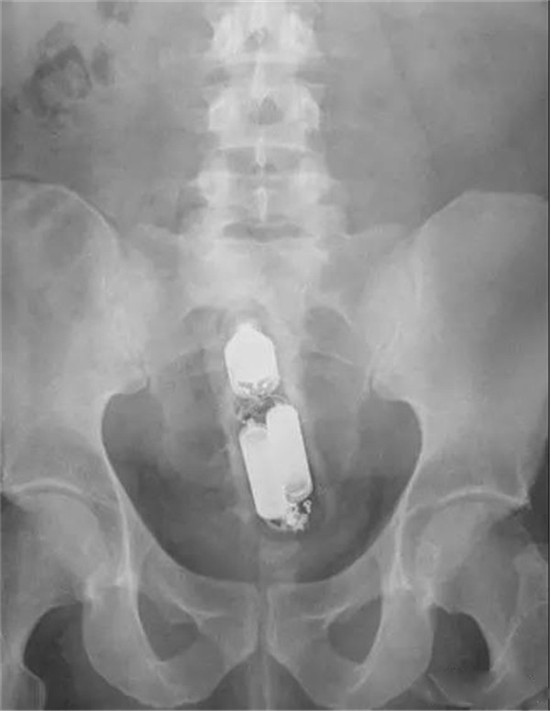

诺基亚3310手机

这是诺基亚3310手机,给这个手机打电话,还能够震动呢。现在的孩子可能已经不知道这个手机了。主人把它塞进去,主要是想利用它的震动功能。